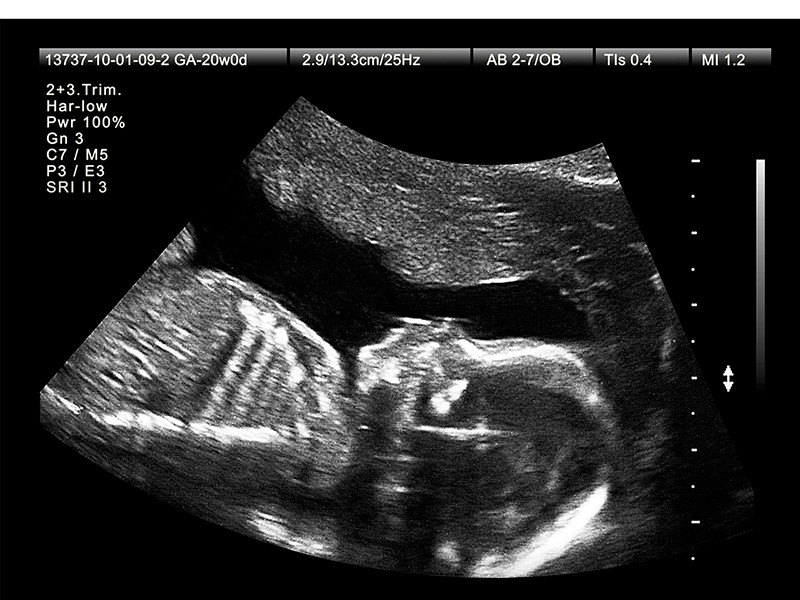

Thông thường, mẹ bầu sẽ được chỉ định siêu âm 4D từ tuần thai 22 đến 28 – giai đoạn em bé đã phát triển đủ về hình thể, lượng nước ối ổn định, và tư thế thai thuận lợi để quan sát rõ nét.

3. Đánh giá sự phát triển của thai nhi

Bác sĩ sẽ đo lường các chỉ số như chiều dài xương đùi, đường kính đầu, chu vi bụng… để so sánh với tuổi thai, từ đó xác định sự phát triển có đúng chuẩn hay không.

Đồng thời, siêu âm 4D cũng kiểm tra:

Lượng nước ối

Vị trí bánh nhau

Dây rốn

Cử động thai

Những thông tin này rất quan trọng để dự đoán nguy cơ thai suy, thiểu ối, dây rốn quấn cổ…